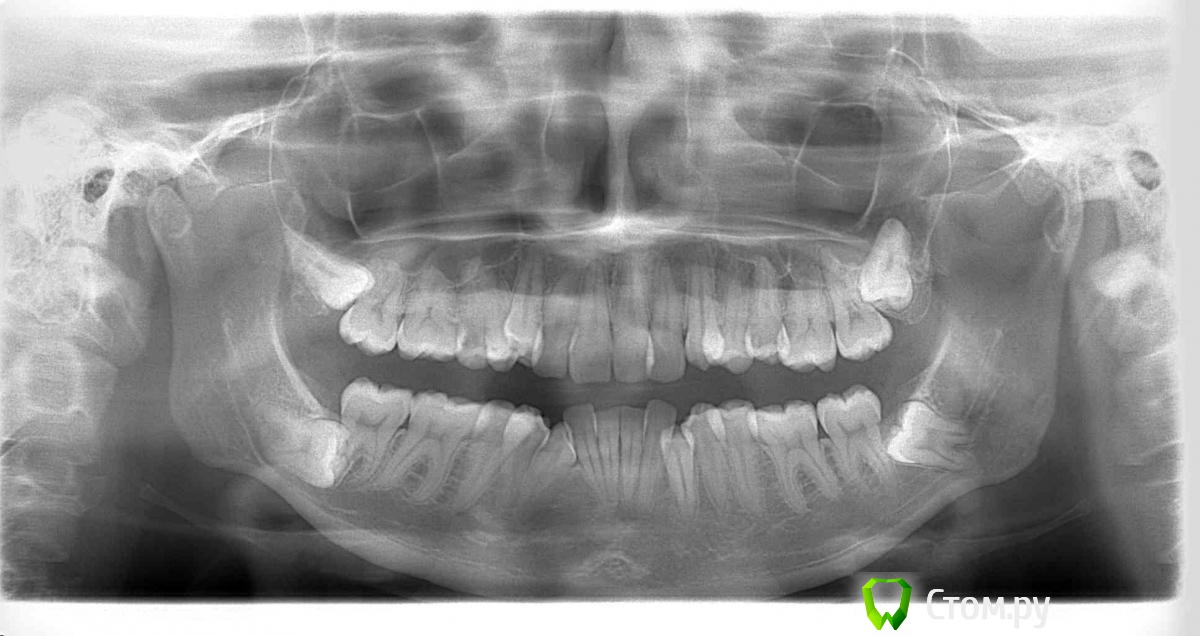

Yuliya88 Опубликовано 23 ноября, 2014 Автор Поделиться Опубликовано 23 ноября, 2014 (изменено) Здравствуйте, у меня сделана только ортопантомограмма. Никаких доп. исследований мне не назначили. Так что можно сказать, что на глазок. Изменено 23 ноября, 2014 пользователем Yuliya88 Ссылка на комментарий